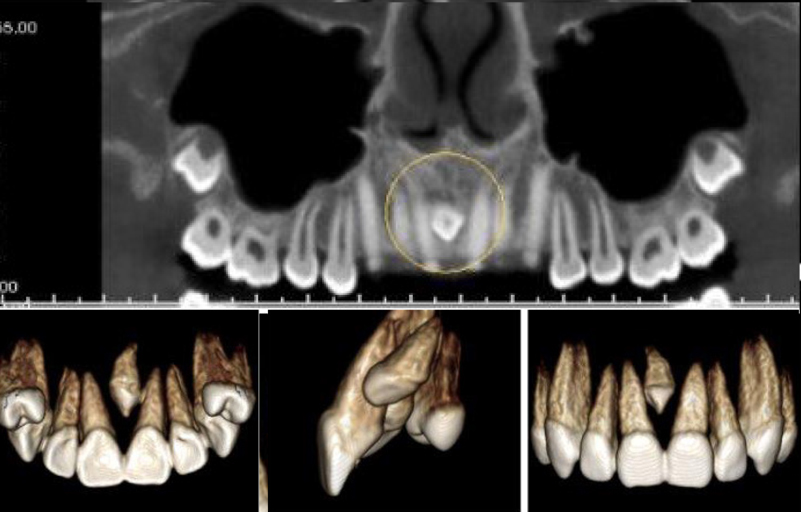

Mesiodens